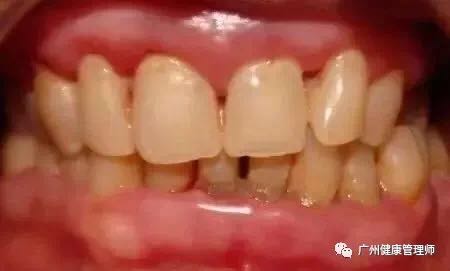

2、牙周疾病。長期口呼吸常伴有前牙,尤其上前牙的菌斑堆積、牙齦發炎??诤粑鼤r會帶走口腔諸多水分,干燥的口腔環境缺少了唾液的機械沖刷和殺菌作用,菌斑堆積,牙齦發炎。而且,鼻呼吸的人唾液呈堿性,而口呼吸的人唾液偏酸,酸性環境也不利于牙齒和牙齦健康。

口呼吸者牙齦紅腫、光亮